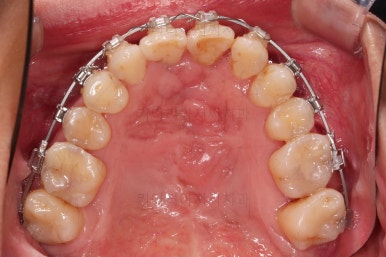

위아래 장치를 부착했습니다.

초기 단계의 주안점은 아랫니와 악궁과 어울리는 윗니 악궁의 형태를 만들어 주는 것이고요.

악궁확장장치를 사용하지 않은만큼 철사의 형태를 잘 잡아가면서 악궁 형태를 개선시킵니다.

교정 10개월째인데, 악궁형태 많이 좋아졌고, 가지런한 느낌도 많이 좋아졌습니다.